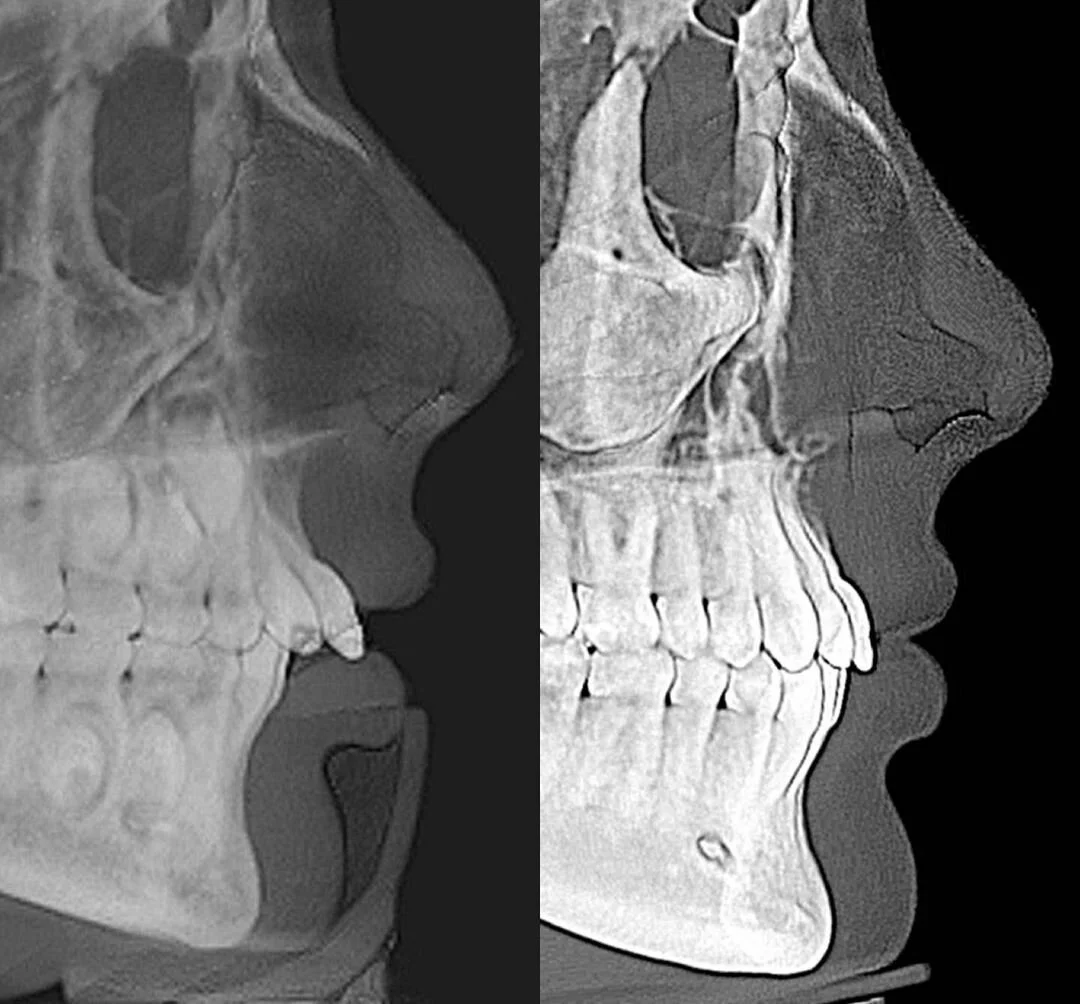

This patient came to intern with Dr. Salzer this week, but as a young girl we treated her using a palate expander and Herbst appliance (for Phase I) and braces (Phase II) to correct her “buck-like” teeth.

Although her upper teeth appeared to be in a good position, there were improvements that were made thanks to orthodontics that allowed us to give her smile more presence.

side profile